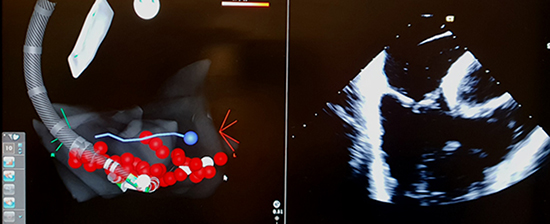

Since the patient had developed Isthmus-dependent AF, the sheath was pulled back to the RA and under ICE guidance was positioned at the CTI. The bidirectional contact sensing ablation catheter was dropped at the CTI and ablation lesions extended from the tricuspid valve all the way to the IVC.

Figure 5. Fluoroscopic view of ablation catheter placement at CTI

Figure 6. Left – CTI Ablation and testing of bidirectional line of block. Right- CTI as visulised on ICE.

Differential pacing was performed on either side of the CTI with confirmation of bidirectional line of block. Attempts to induce recurrent tachycardia with burst pacing were unsuccessful.